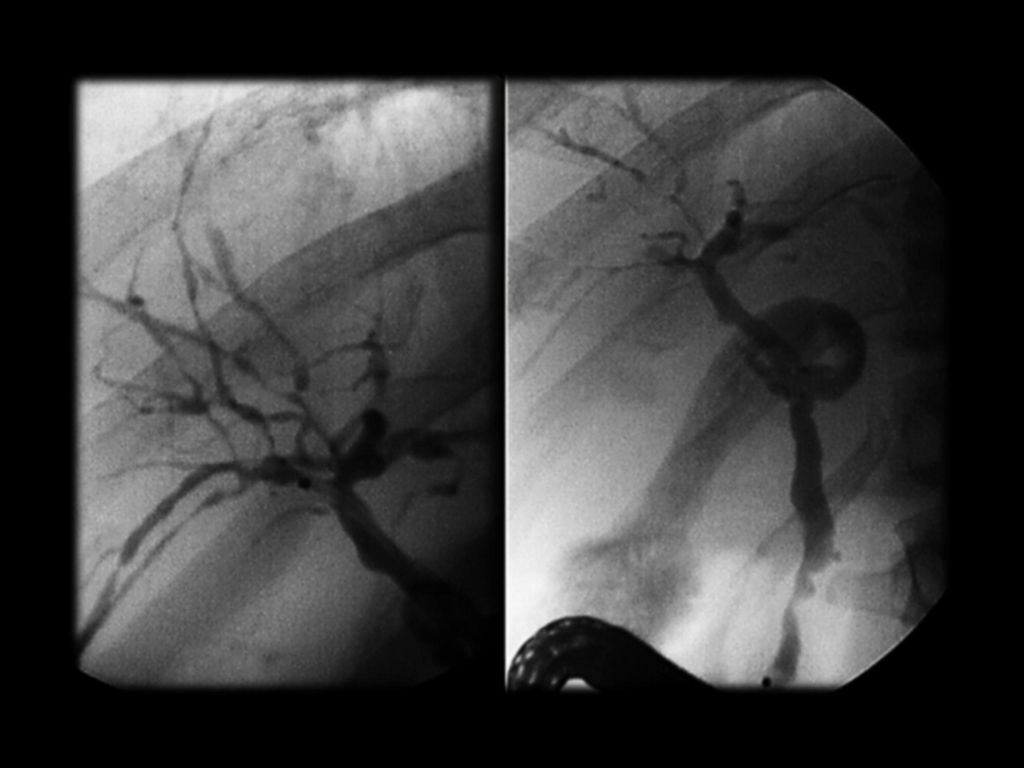

Фотографии и изображения, связанные с симптомами первичного склерозирующего холангита